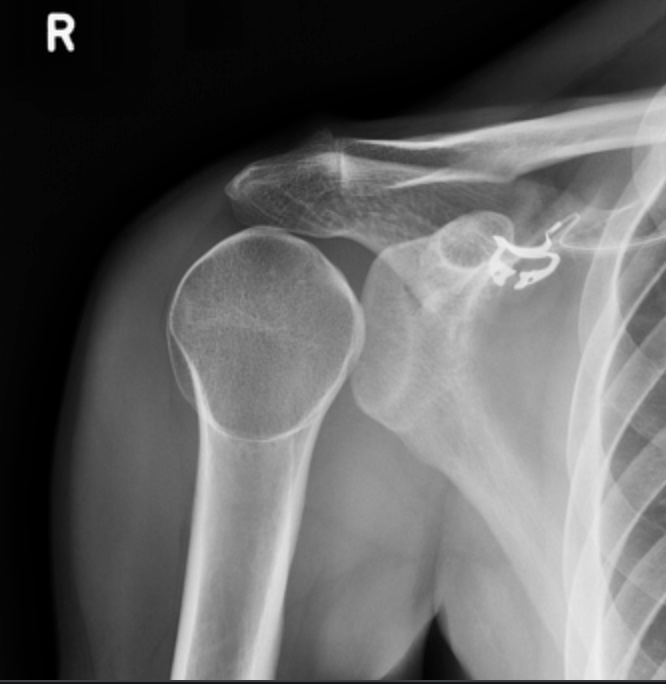

Remember to look at the acromioclavicular joint (ACJ)

In trauma setting, there may be stretching/rupture of the acromioclavicular and/or coracoclavicular ligaments leading to disruption of the ACJ.

Clues pointing to ACJ disruption:

– Inferior cortices of the clavicle and acromion do not align.

– Acromioclavicular (AC) distance > 8 mm

– Coracoclavicular (CC) distance > 1.3 cm

(Note: There may be variation of the CC distance in different individuals, comparison with the contralateral side may be more useful than the absolute value itself. There should no be more than 5 mm difference between both sides in a normal ACJ)

Rockwood classification of AC joint disruption

• Type I: Normal radiographic appearance

• Type II: Widened ACJ (> 7 mm) with < 25% clavicular elevation

• Type III: Clavicle elevated above the superior border of the acromion but the CC distance is less than twice normal (i.e. <25 mm) or 5mm greater than this distance on the contralateral side

• Type IV: Clavicle displaced posteriorly

• Type V: Clavicle is markedly elevated and coracoclavicular distance is more than double normal (i.e. >25 mm) – bilateral weight-bearing projections are able to distinguish type V injuries

• Type VI: Inferior displacement of clavicle